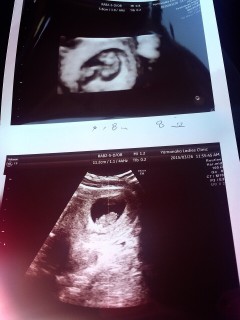

8週目に入った時のエコーです(≧∇≦) ピコピコ動いていてクリオネみたいでした♡ 自分の体の中に別の命が宿ってると思うと すごく不思議で幸せな気持ちになります。

周りに見せると双子と言われます(^^) 双子でしょうか?